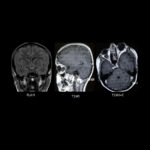

Neurosurgery and neuroradiology always go hand in hand. This little weekly activity is going to enhance the scan reading skills of our audience in an interactive way. Waiting for the answer for a week will keep the curiosity alive and will keep our target audience hooked to the website. It will prove to be a seamless share of knowledge and reading skills.

Dr. Saqib Kamran Bakhshi started the PANS Weekly Image Challenge in 2022, and his creativity and efforts made it a popular activity; engaging trainees and consultants in Pakistan and abroad.